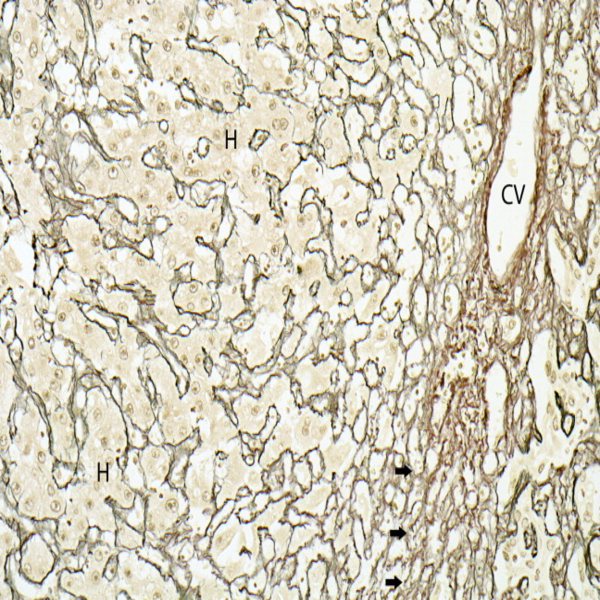

- Immunohistochemistry (IHC) technique

Histological methods includes sample processing in the pathology laboratory, preparation of the slide and its examination under a microscope, sample fixation, molding, microtome cutting, staining and assembly of the slides.